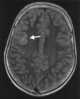

Measles encephalitis

Measles is a highly contagious infectious disease caused by measles virus. Symptoms usually develop 10–12 days after exposure to an infected person and last 7–10 days. [Source: Wikipedia ]